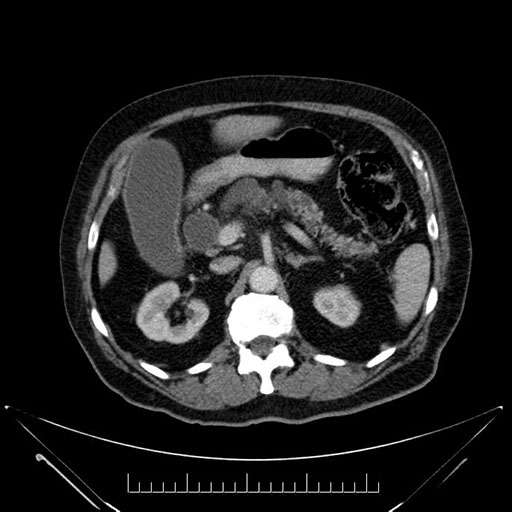

Whipple (pancreaticoduodenectomy) [case 7]

Imaging Analysis

Look through the patient's CT scan to identify any areas of concern for the necessary procedure.

Based on your CT findings, which issue(s) would give reason for "planned slowing down moment(s)" in this case?

Considering a standard Whipple procedure, what step(s) of the operation would you do differently in this case?